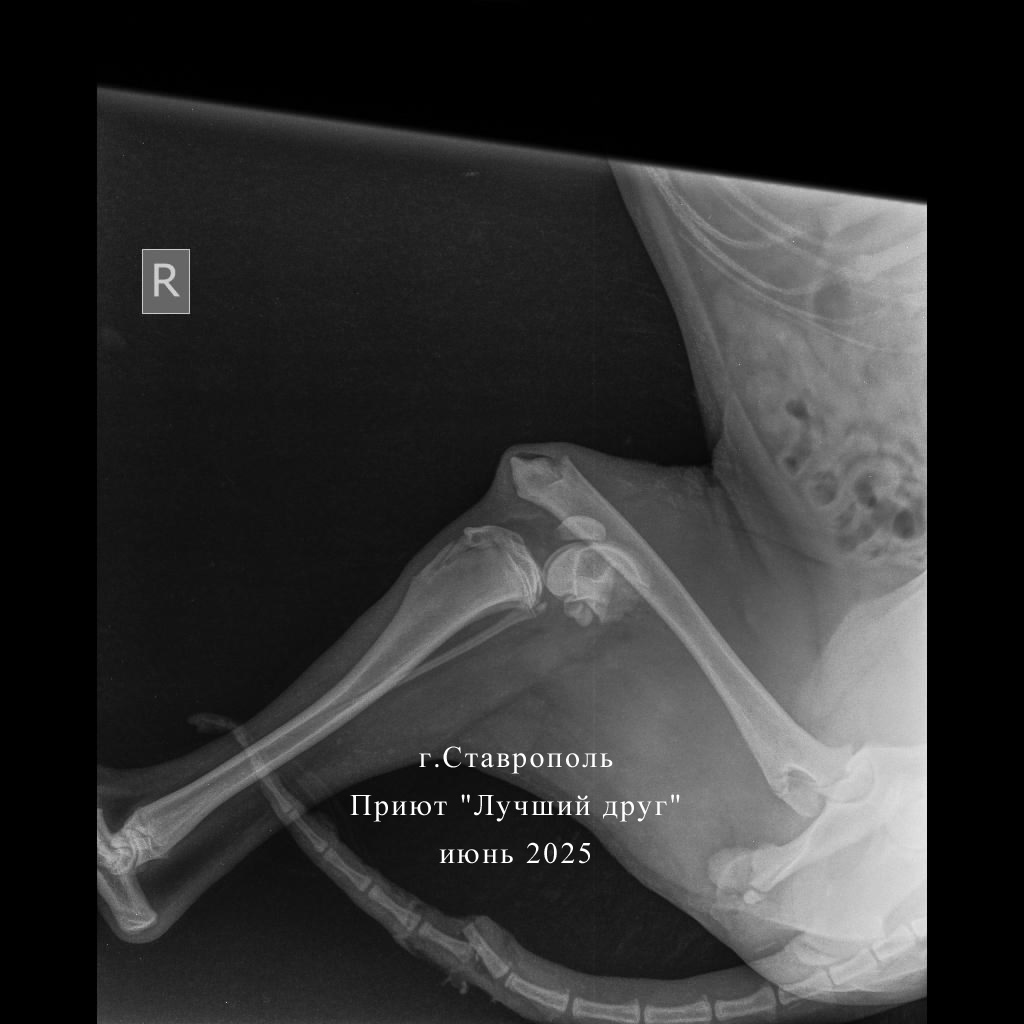

Читая истории спасения собак, поневоле задумываешься, насколько повезло животному, что кто-то его нашел вовремя и смог оказать помощь. Заре не повезло. Она три дня после ДТП валялась в кустах в беспомощном состоянии. И когда ее все-таки привезли в клинику к множественным травмам и переломам уже добавились некрозы, нагноения. Поэтому в клинике сначала провели экстренные мероприятия: обработали и максимально зачистили раны и ампутировали сгнивший хвост. И только после курса антибиотиков, несмотря на то, что по общему анализу крови анемия, взялись оперировать переломы, ждать дольше нельзя, собака рискует остаться инвалидом.

Читая истории спасения собак, поневоле задумываешься, насколько повезло животному, что кто-то его нашел вовремя и смог оказать помощь. Заре не повезло. Она три дня после ДТП валялась в кустах в беспомощном состоянии. И когда ее все-таки привезли в клинику к множественным травмам и переломам уже добавились некрозы, нагноения.

Поэтому в клинике сначала провели экстренные мероприятия: обработали и максимально зачистили раны и ампутировали сгнивший хвост. И только после курса антибиотиков, несмотря на то, что по общему анализу крови анемия, взялись оперировать переломы, ждать дольше нельзя, собака рискует остаться инвалидом.

Вчера, 17 июня, Зарю прооперировали, в выписке много медицинских терминов, но если перевести на общепонятный язык - собрали сломанные кости задних лап и было это очень непросто. Сейчас Заря отошла от наркоза и остается под наблюдением врачей.